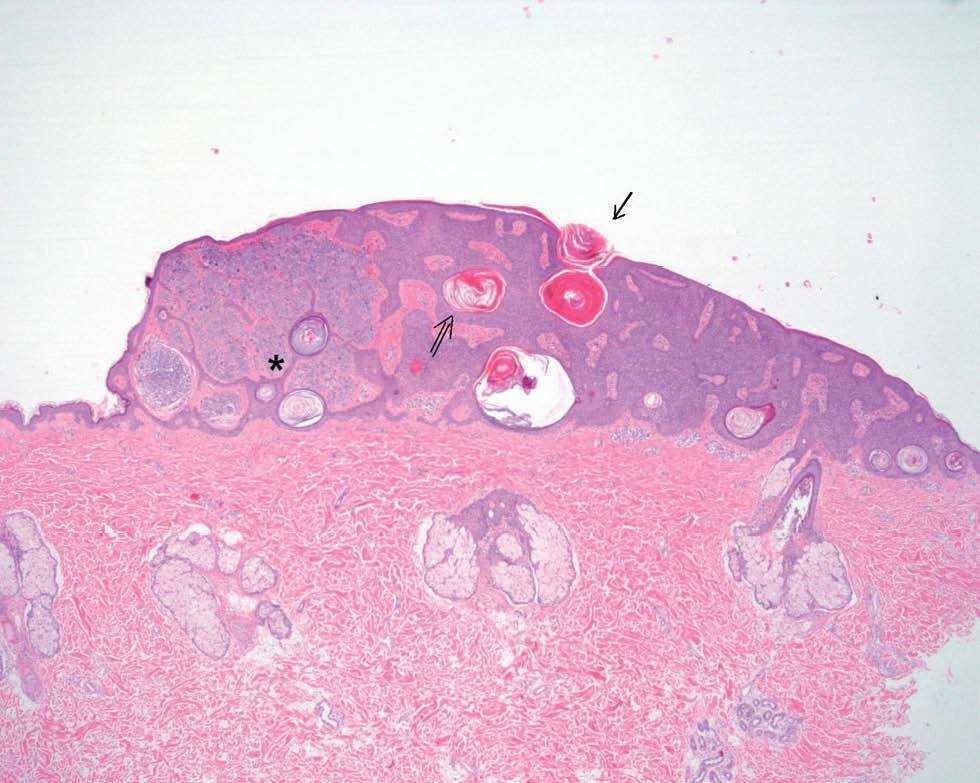

Fig. 3.--Cúmulos de queratina intraepidérmicos sin comunicación con el exterior (⇒) y abiertos a la superficie (→). Numerosas tecas de melanocitos en dermis (*).

En el estudio anatomopatológico se observaron hallazgos que se correlacionan con los encontrados en la dermatoscopia (fig. 3). La presencia de cúmulos de queratina intraepidérmica sin comunicación con el exterior corresponde a los quistes, y los que alcanzan la superficie cutánea a las pseudoaperturas foliculares. Los glóbulos marrones observados mediante dermatoscopia corresponden a los distintos nidos de melanocitos situados en la dermis.